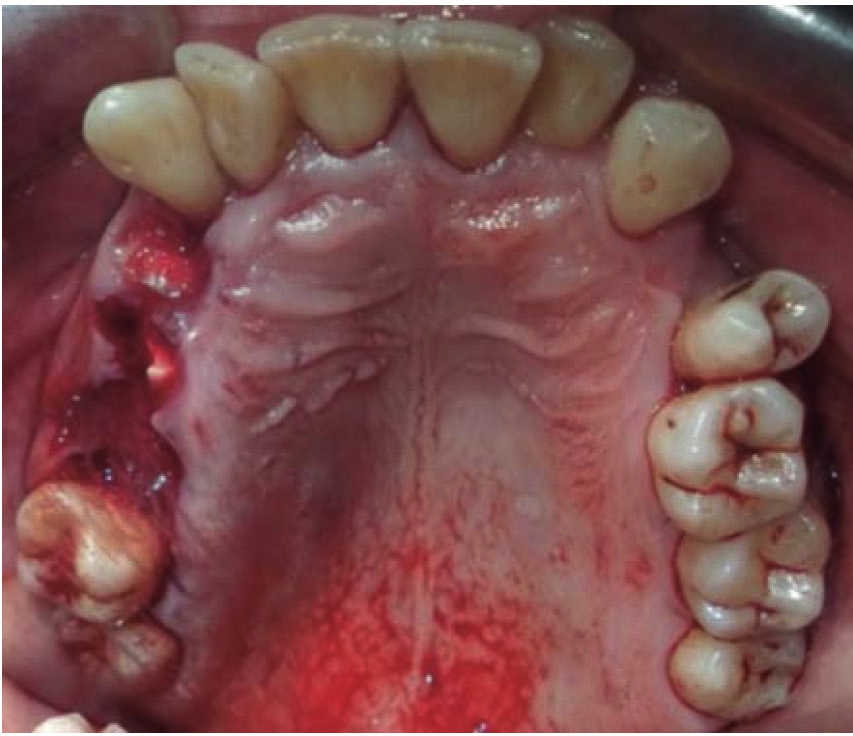

Masculino de 48 años con diagnóstico de herida facial por arma de fuego. Es agredido por tercera persona en vía pública. No refiere distancia de disparo. El paciente presenta una herida de entrada de proyectil a nivel de región geniana derecha sin orificio de salida (Figura 8). Intraoralmente se observa herida en carrillo derecho, fractura dental a nivel de la hemiarcada superior derecha: con primer premolar, segundo premolar y primer molar con fractura a nivel de cuello dental (Figuras 9 y 10). En lengua se observa herida penetrante donde se palpa zona central indurada. Vía aérea estable, sin compromiso sistémico. Mediante anestesia local se lava herida con jabón quirúrgico y abundante solución fisiológica. Se diseca en lengua de manera superficial, se extrae bala (Figura 11), se realiza hemostasia y se suturan heridas. Los remanentes dentales se consideran restos no aptos para restaurarse por lo que se extraen. Acude a valoraciones periódicas, con adecuada cicatrización de heridas de tejidos blandos y proceso alveolar. Paciente niega opción de implantes dentales por costo, por lo que se extiende el pase para su rehabilitación mediante prótesis removible.

En los tres casos presentados se inicia con valoración cardiopulmonar, manejo de vía aérea, control hemodinámico, ventilación, discapacidad neurológica y daños específicos.9-11 Con la exploración física determinamos la extensión de daño en los tejidos, presencia de orificios de entrada y salida para descartar la presencia de bala al interior en una cavidad o tejido (caso 2). El manejo maxilofacial se inicia con desbridaje conservador, lavado, extracción de restos radiculares, sutura y estabilización oclusal. La reducción y fijación de las fracturas (caso 1 y 3) se realizó en un segundo acto quirúrgico con placas de reconstrucción. En los casos expuestos se observó una buena evolución, una cicatriz ósea favorable y la necesidad de continuar con una rehabilitación oral mediante prótesis o implantes osteointegrados. Las complicaciones y secuelas son comunes y surgen por lo general a causa de la severidad de las lesiones iniciales, retraso en el tratamiento por riesgo vital o estado sistémico del paciente.